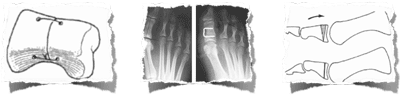

RADIOGRAPHIE

3 stades radiographiques

( cliniquement : hallux dolorosus)

( douleur et enraidissement articulaire)